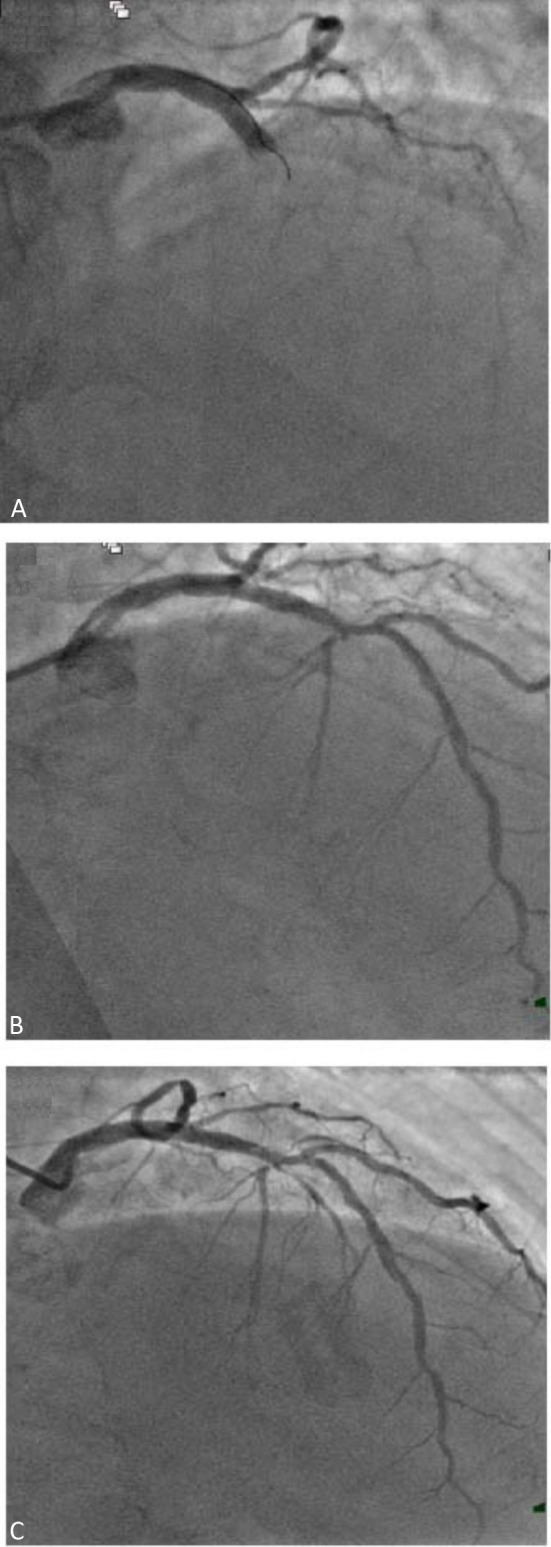

Figures 1 and 2 show the angiographic results (immediately post-PCI and on relook coronary angiogram) of 2 patients with anterior STEMI treated with Selution SLRTM DCBs.

Figure 1.

The patient was a 68 year old gentleman who was admitted for anterior myocardial infarction (MI). (A) Initial coronary angiogram showing an occluded mid left anterior descending artery (LAD). (B) Immediate post percutaneous coronary intervention (PCI) result after drug-coated balloon (DCB) angioplasty with Selution SLR. (C) Re-look coronary angiogram 3 months later.